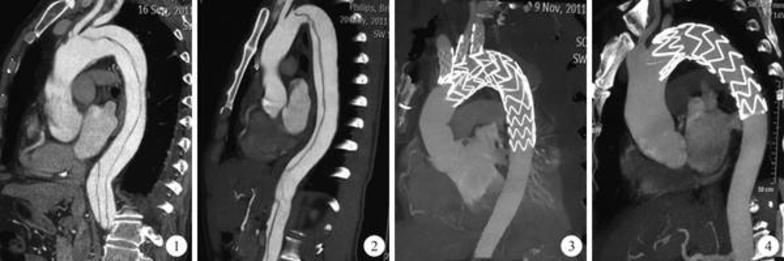

内科介入治疗:覆膜支架植入术封闭内膜破口和压闭假腔。

外科开胸人工血管置换。